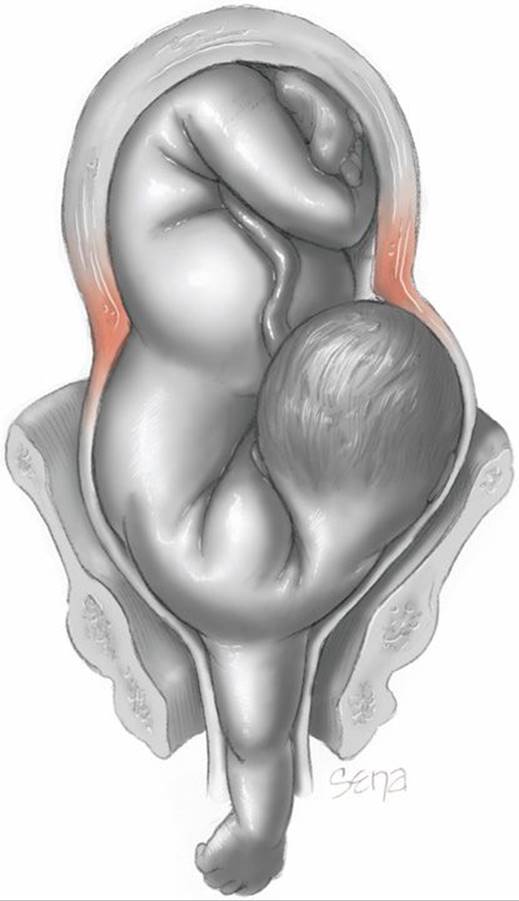

Spontaneous delivery of a fully developed newborn is impossible with a persistent transverse lie. After rupture of the membranes, if labor continues, the fetal shoulder is forced into the pelvis, and the corresponding arm frequently prolapses (Fig. 23-10). After some descent, the shoulder is arrested by the margins of the pelvic inlet, with the head in one iliac fossa and the breech in the other. As labor continues, the shoulder is impacted firmly in the upper part of the pelvis. The uterus then contracts vigorously in an unsuccessful attempt to overcome the obstacle. With time, a retraction ring rises increasingly higher and becomes more marked. With this neglected transverse lie, the uterus will eventually rupture. Even without this complication, morbidity is increased because of the frequent association with placenta previa, the increased likelihood of cord prolapse, and the necessity for major operative efforts.

FIGURE 23-10 Neglected shoulder presentation. A thick muscular band forming a pathological retraction ring has developed just above the thin lower uterine segment. The force generated during a uterine contraction is directed centripetally at and above the level of the pathological retraction ring. This serves to stretch further and possibly to rupture the thin lower segment below the retraction ring.